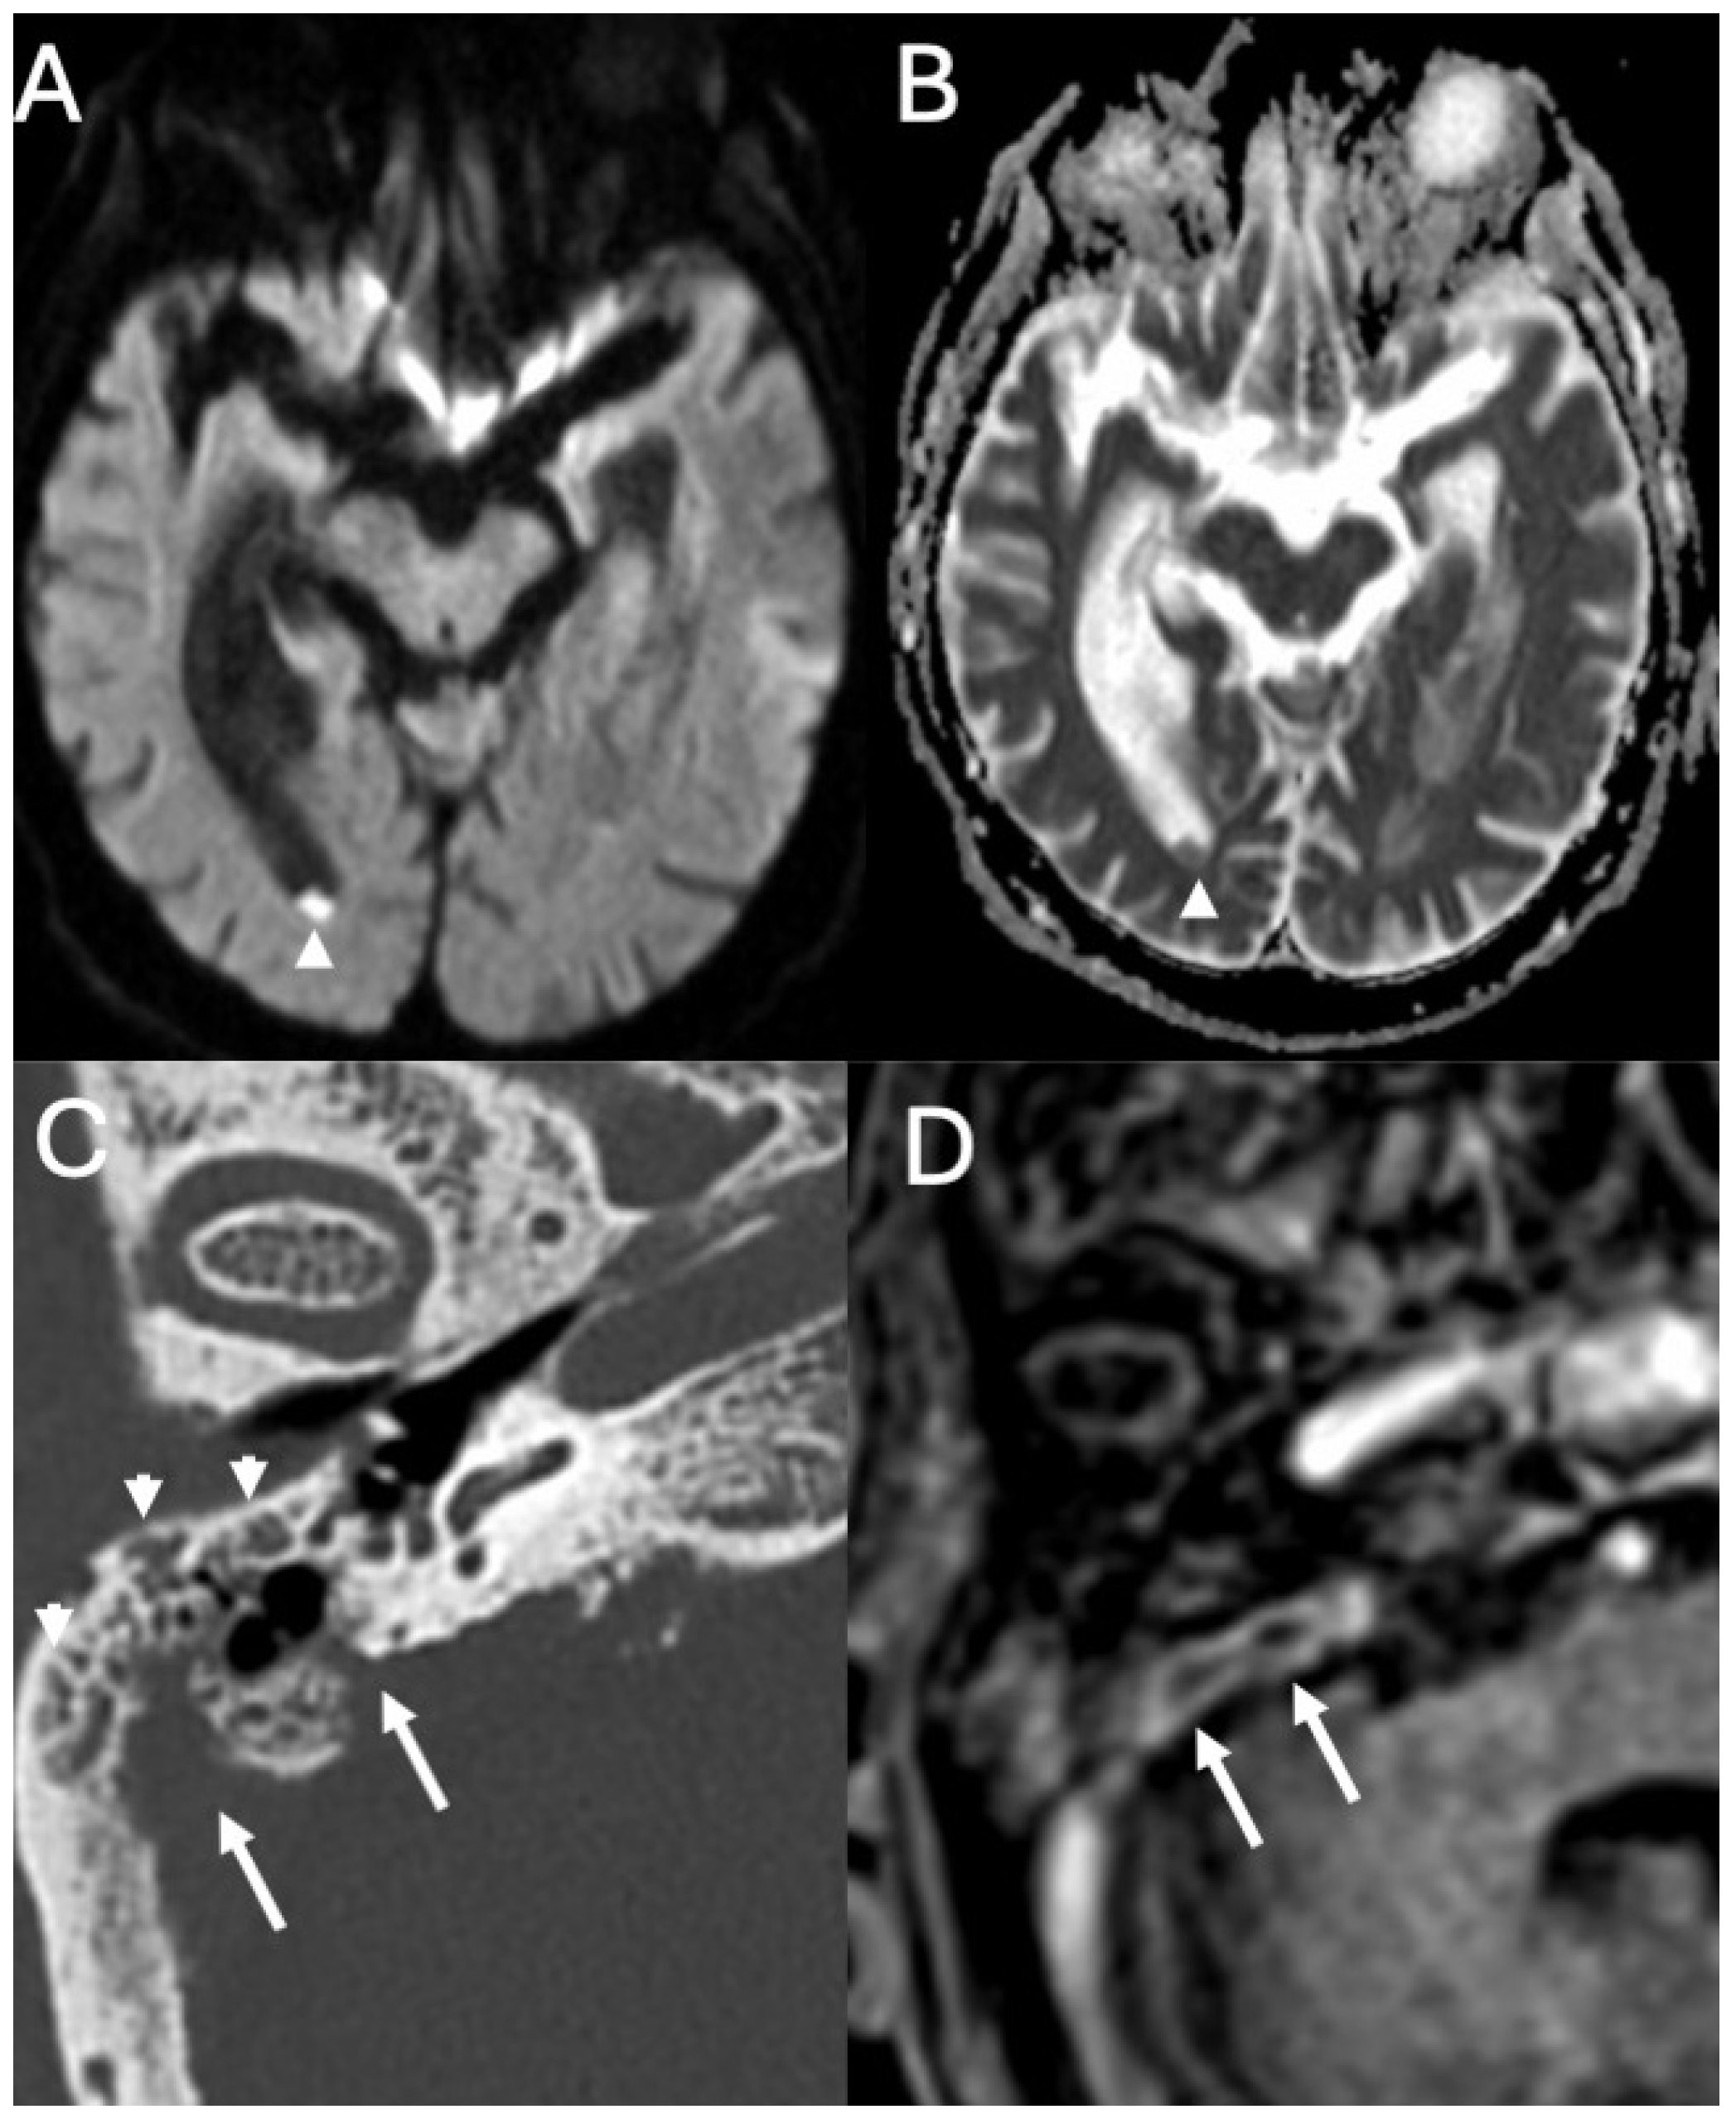

3.4. Labyrinthitis and Vestibulocochlear Neuritis

Imaging

3.5. Cochlear Hemorrhage

| Labyrinthitis/Vestibulocochlear Neuritis | Taxak & Ram 2020 [32]; Kharrat et al., 2024 [33]; Singh et al., 2023 [34]; Kim et al., 2024 [35] | Case reports and small series | Meningitis can cause secondary labyrinthitis with cochlear enhancement on MRI; progression to ossification possible if chronic. |

| Cochlear Hemorrhage (Rare Complication) | Perillo et al., 2024 [36]; Engelen-Lee et al., 2016 [37] | Case report; pathologic correlation study | First documented case of cochlear hemorrhage secondary to pneumococcal meningitis; likely due to microvascular injury. |